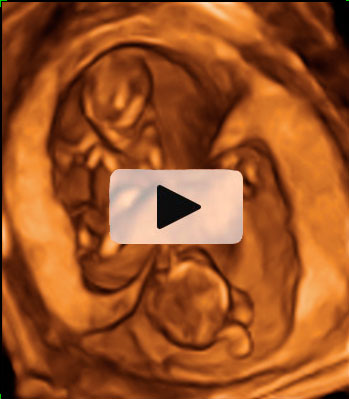

Ecografía semana 12 de embarazo gemelar

Los bebés tiene la cabeza en direcciones opuestas

Ecografía 4D de gemelos de 12 semanas "contrapeados": Cada uno de los bebés está con la cabeza en una dirección, tal y como podemos visualizar en el ultrasonido. Uno de los gemelos se mueve al final de las imágenes de la ecografía mientras su hermano descansa.

Ecografía en 4D de gemelos de 12 semanas "contrapeados"

Cada gemelo está con la cabeza en una dirección, tal y como se aprecia en esta ecografía en 4D. Los dos fetos "contrapeados" tienen bolsas y placentas independientes. Destaca el movimiento del gemelo que aparece en la parte superior de la imagen: pareciera que se "arranca" a bailar al final del vídeo, mientras que su hermano permanece más tranquilo en su bolsa.